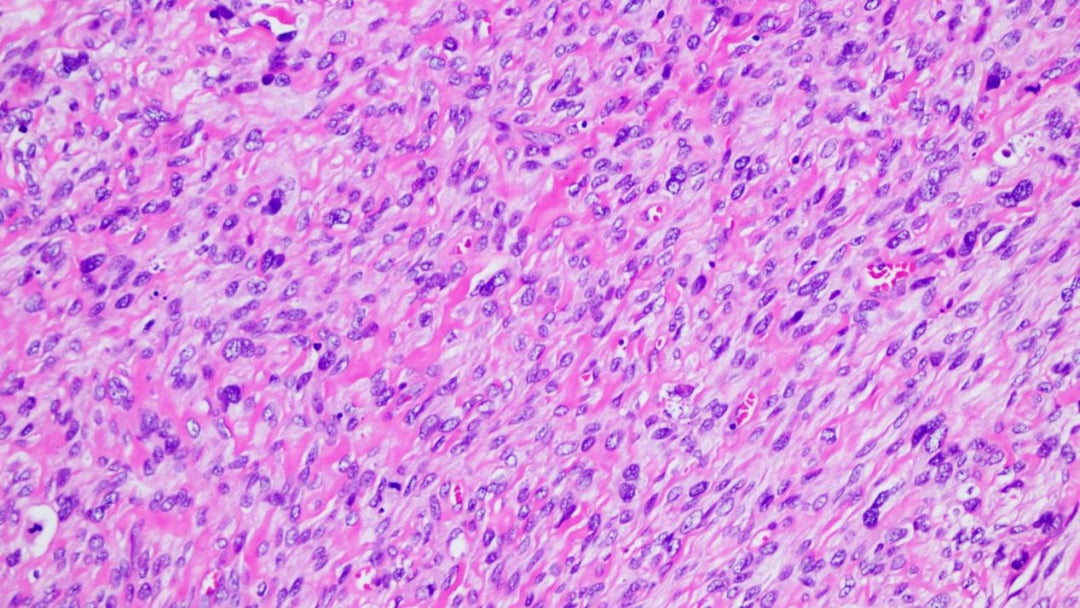

高倍镜下,肿瘤细胞高度异型性,可见多个病理性核分裂象

- 高度恶性特征:肿瘤细胞表现出高度的异型性,细胞大小不一,核深染,形态怪异。病理性的核分裂象(癌细胞分裂的标志)随处可见,这预示着肿瘤具有很强的增殖和侵袭能力。

- 细胞形态多样:肿瘤组织由多种形态的细胞构成。大部分区域由交织分布的梭形细胞组成,呈现出纤维肉瘤样的外观;部分区域则呈现血管外皮瘤样结构;还有少部分卵圆形细胞围绕在骨样和软骨样基质周围。